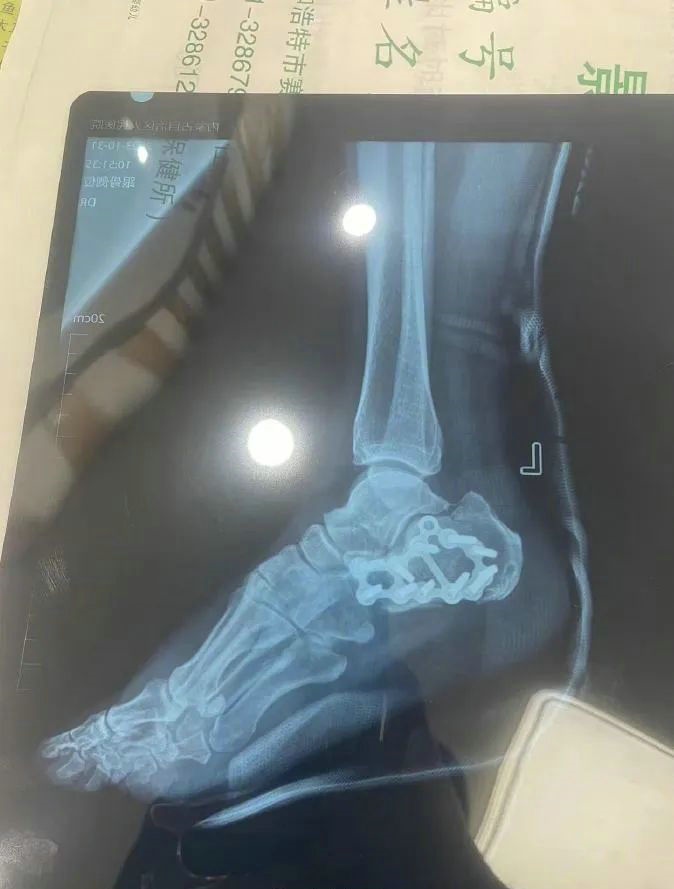

“那時(shí)候我剛工作了兩天,在第三天10月22日下午施工過(guò)程中從三層高的鐵架上摔了下來(lái),導(dǎo)致30厘米左右的鋼筋刺穿我的右側(cè)臀部,左腳跟也粉碎性骨折,被送往內(nèi)蒙古自治區(qū)人民醫(yī)院救治,當(dāng)晚做了手術(shù)取出刺在右臀部的鋼筋,10月30日又進(jìn)行了左腳粉碎性骨折手術(shù)。”雷先生告訴記者。